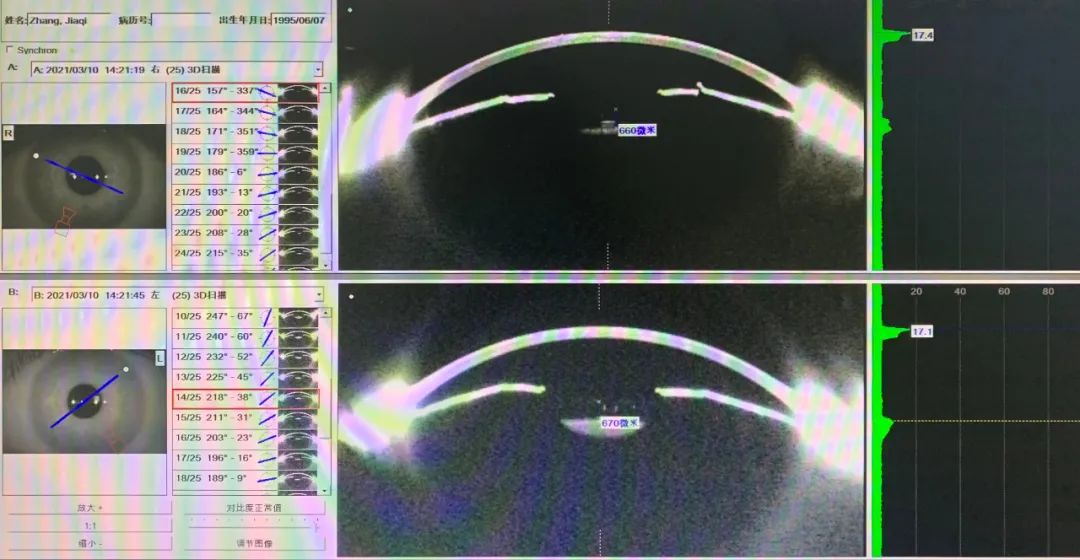

女26岁,双眼高度散光,右-6.25/-3.50x5,左-5.50/-3.00x175。右CD11.2 ACD3.44 LT2.98,左CD11.2 ACD3.37 LT3.01。右STS11.5(水平)-12.12(垂直),左STS11.5(水平)-11.82(垂直)。UBM显示:双眼STS并不大,右睫状沟宽。根据CD与ACD,系统推荐12.6,考虑STS仅11.5,左眼选择12.1水平植入,而右眼睫状沟较宽,选12.1ICL可能下移,拱高变小及影响高散的稳定性,故设计右12.6垂直位植入,按-6.25/-3.50x95订片。术后拱高右眼660,左眼670。

图3-1

图3-2

图3-3